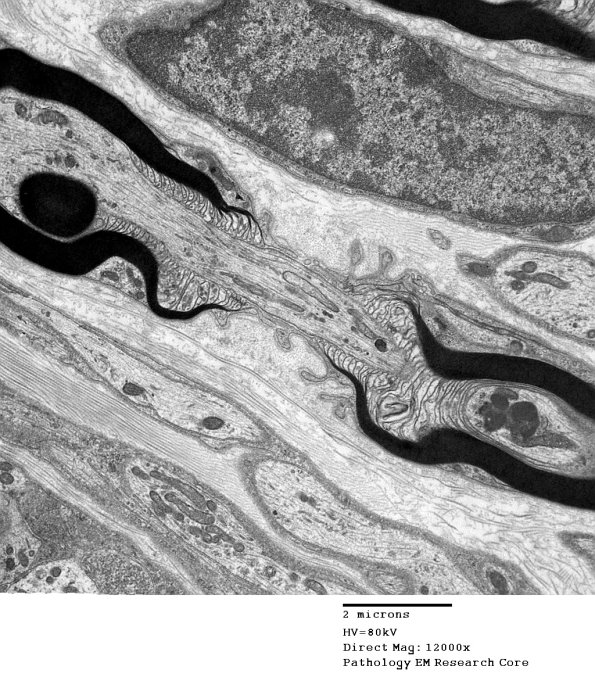

Washington University Experience | PERIPHERAL NEUROPATHY | 3 NORMAL MYELIN & SCHWANN CELLS | 2 Node of Ranvier | 11A2 Normal Node of Ranvier (Case 9) EM A_168 - Copy

11A2 Normal Node of Ranvier (Case 9) EM A_168 - Copy

Higher magnification of image #11A1. (electron micrograph)